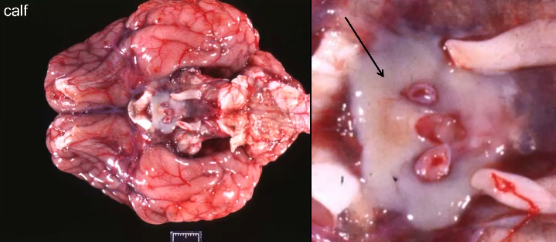

Name the disease

*Hint: this pathogen entered the cat via direct extension

Feline CNS cuterebriasis